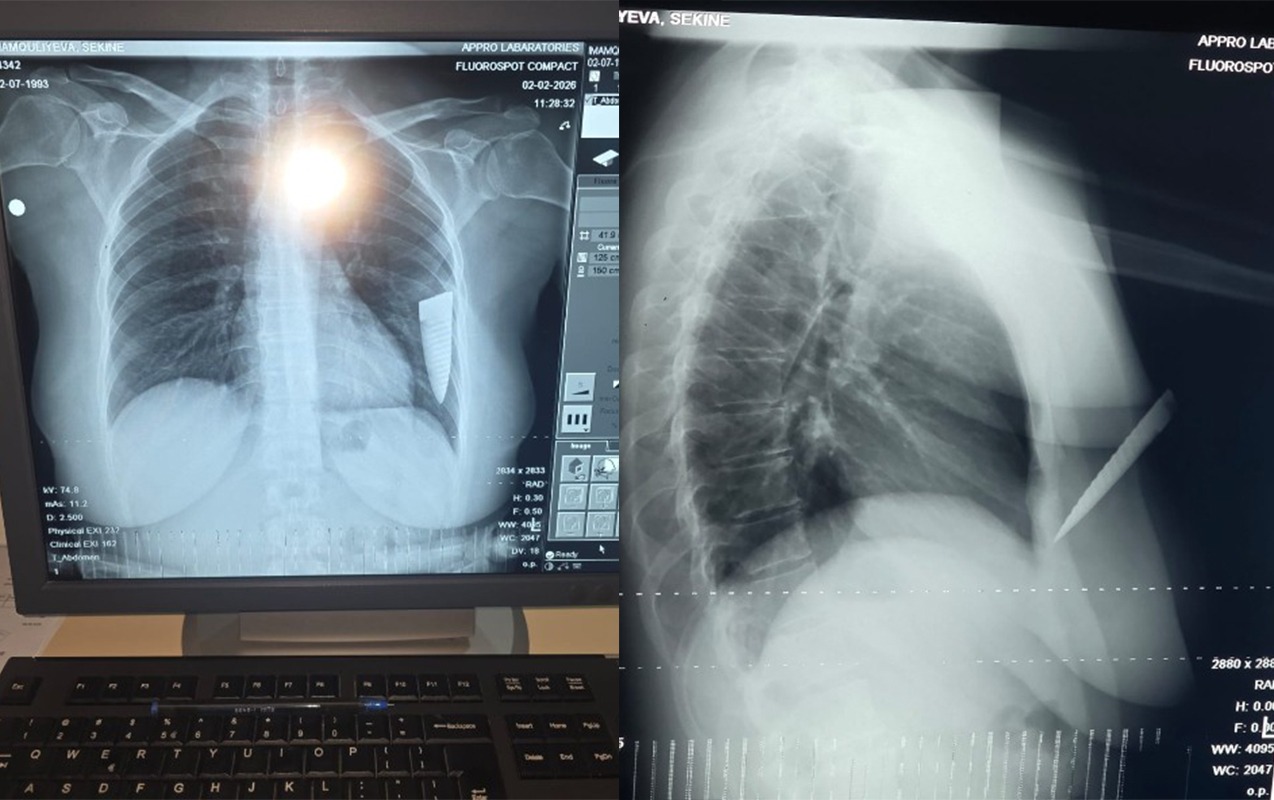

Он внезапно подошел к автомобилю, открыл переднюю правую дверь и начал меня душить, схватив за горло. Затем он достал из кармана нож и нанес мне 4 удара. Один удар пришелся в область сердца, остальные три - в левую руку. В тот момент лезвие ножа сломалось и осталось у меня в грудной клетке. Если бы не это, он мог бы нанести еще больше ударов и убить меня, так как бил ножом непрерывно. Увидев, что нож сломался, а на шум сбегаются люди, он скрылся с места происшествия”, - сообщила пострадавшая.

По словам С.Имамгулиевой, причиной инцидента стало ее расставание с возлюбленным: “Нашим отношениям пришел конец. Али после расставания регулярно преследовал меня и угрожал. После того как он нанес мне ножевое ранение, меня доставили в Шамкирскую центральную районную больницу, а оттуда – в госпиталь в Гяндже, где прооперировали. Часть ножа, сломавшаяся и оставшаяся в моей грудной клетке, была удалена хирургическим путем. В настоящее время из-за серьезных осложнений со здоровьем я не могу работать. В результате инцидента я понесла огромный материальный и моральный ущерб, а противоположная сторона даже не интересуется моим состоянием”.